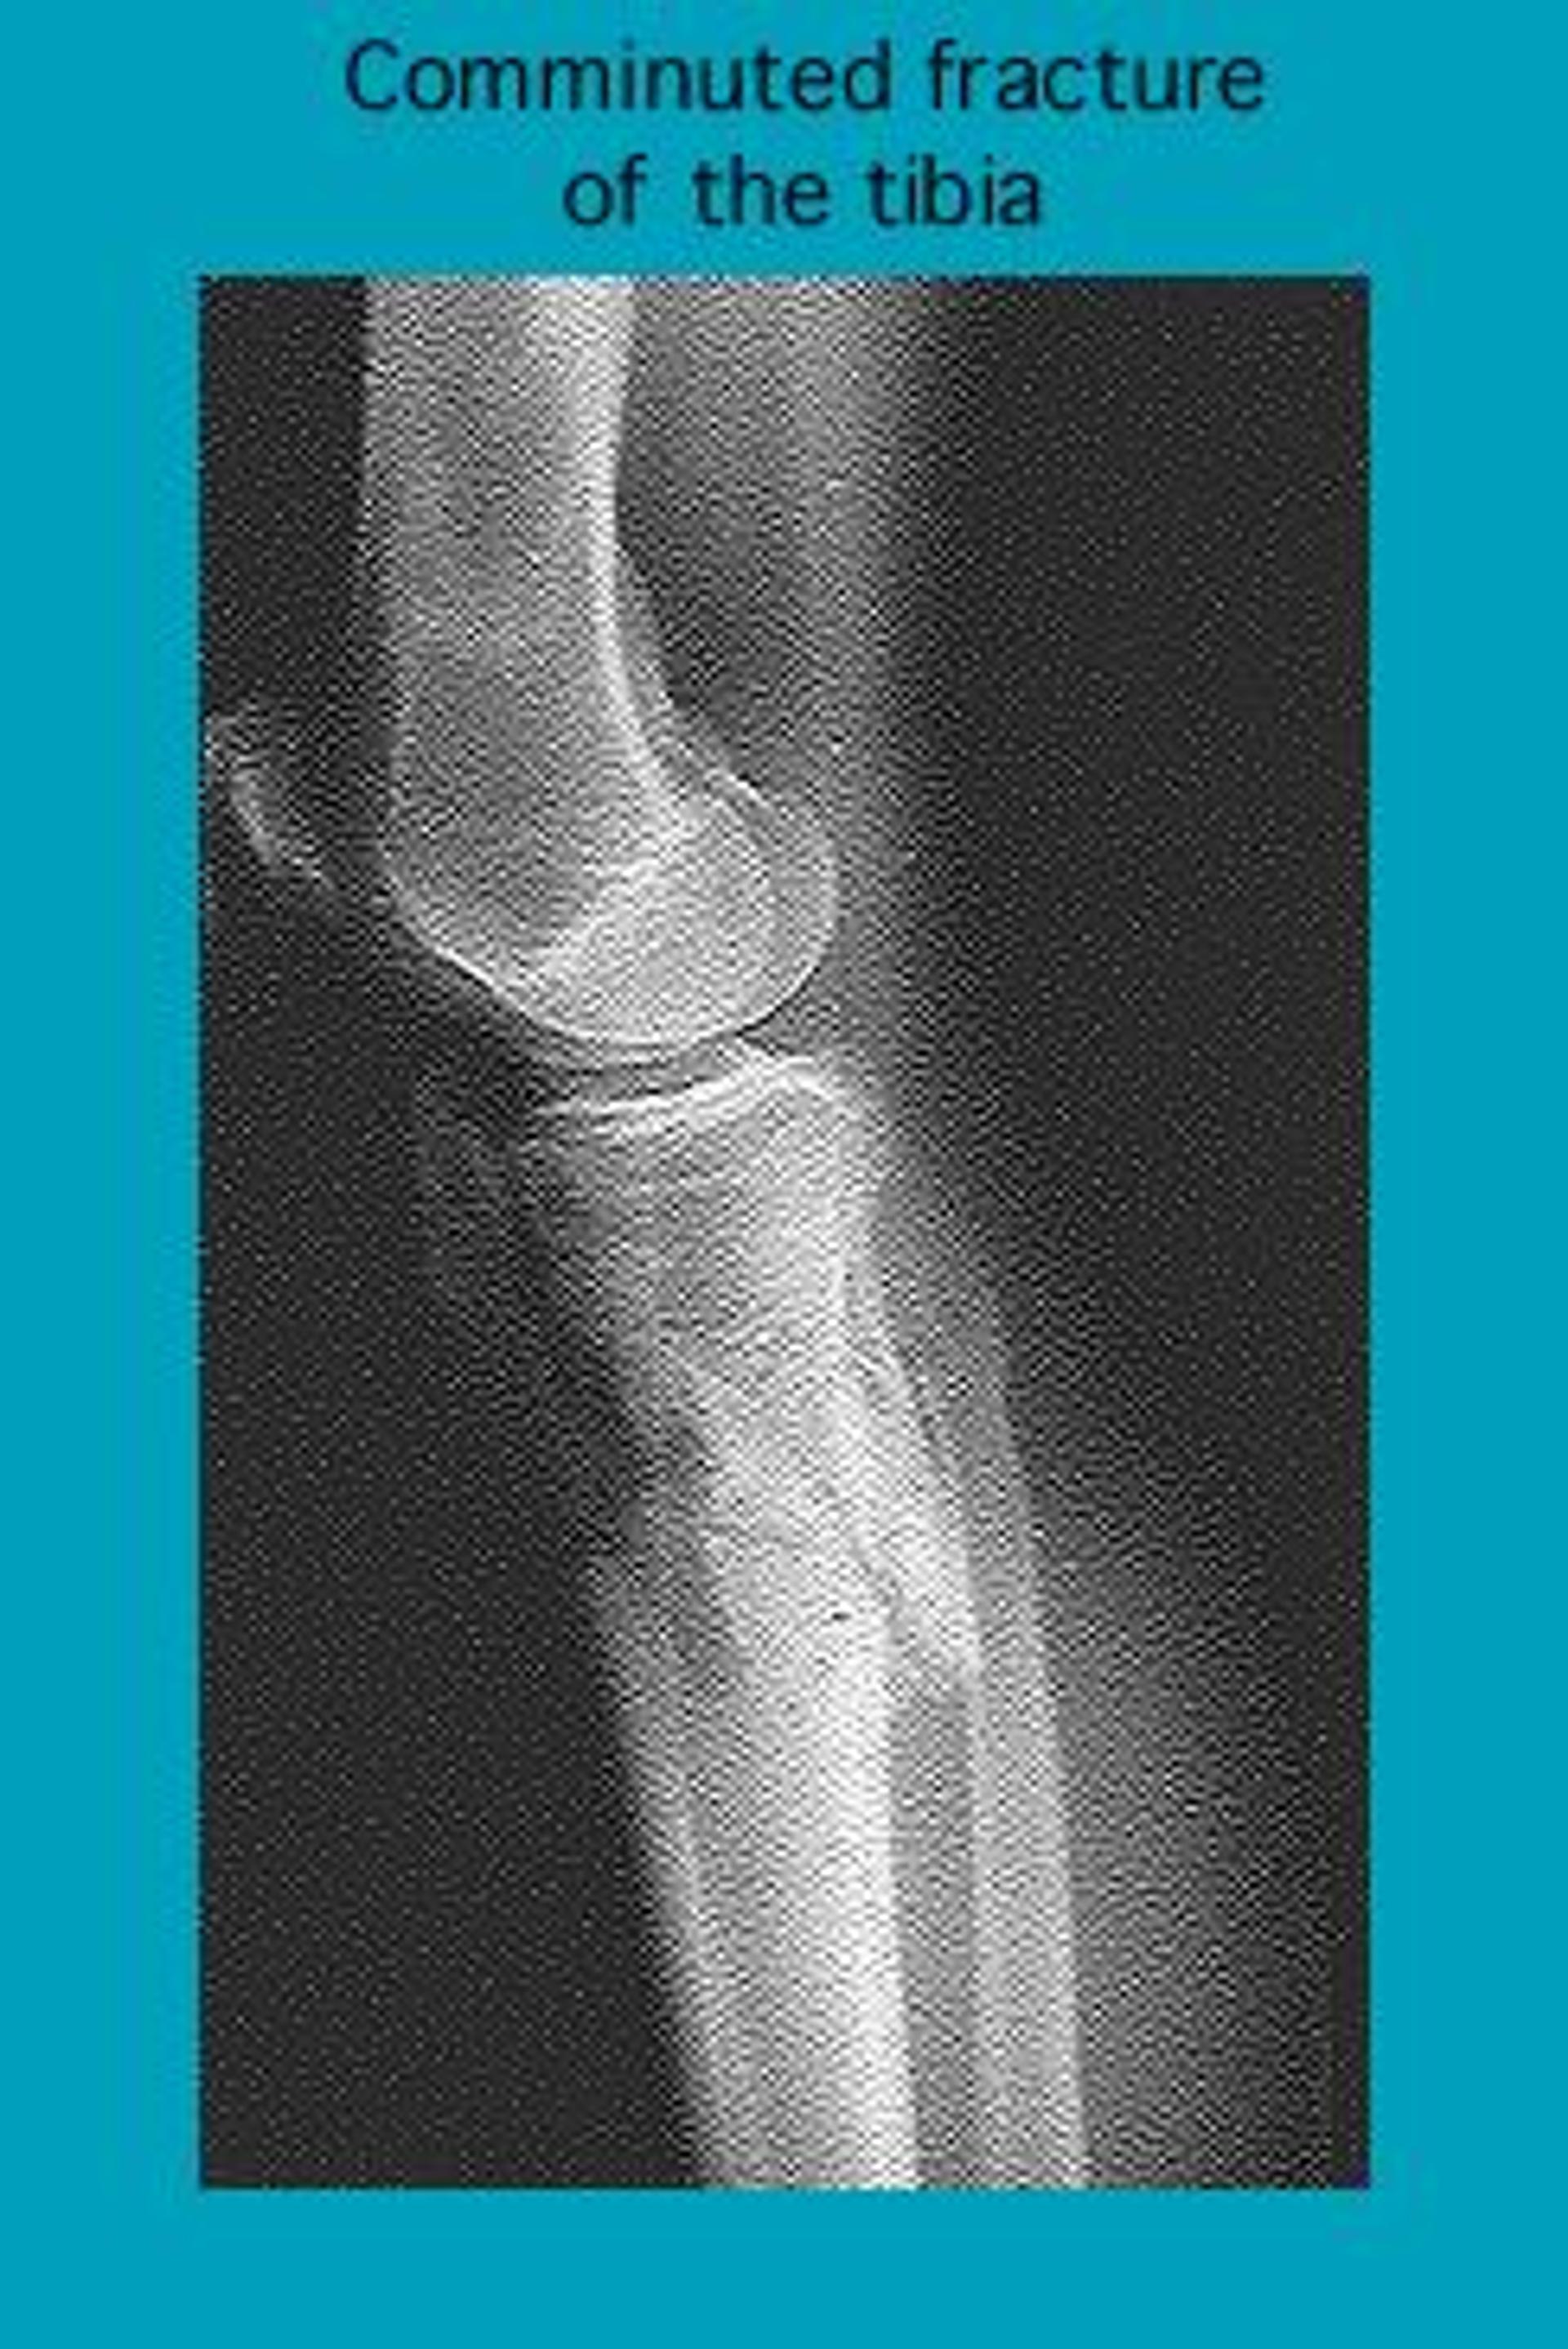

Röntgenbild einer Trümmerfraktur des Schienbeins